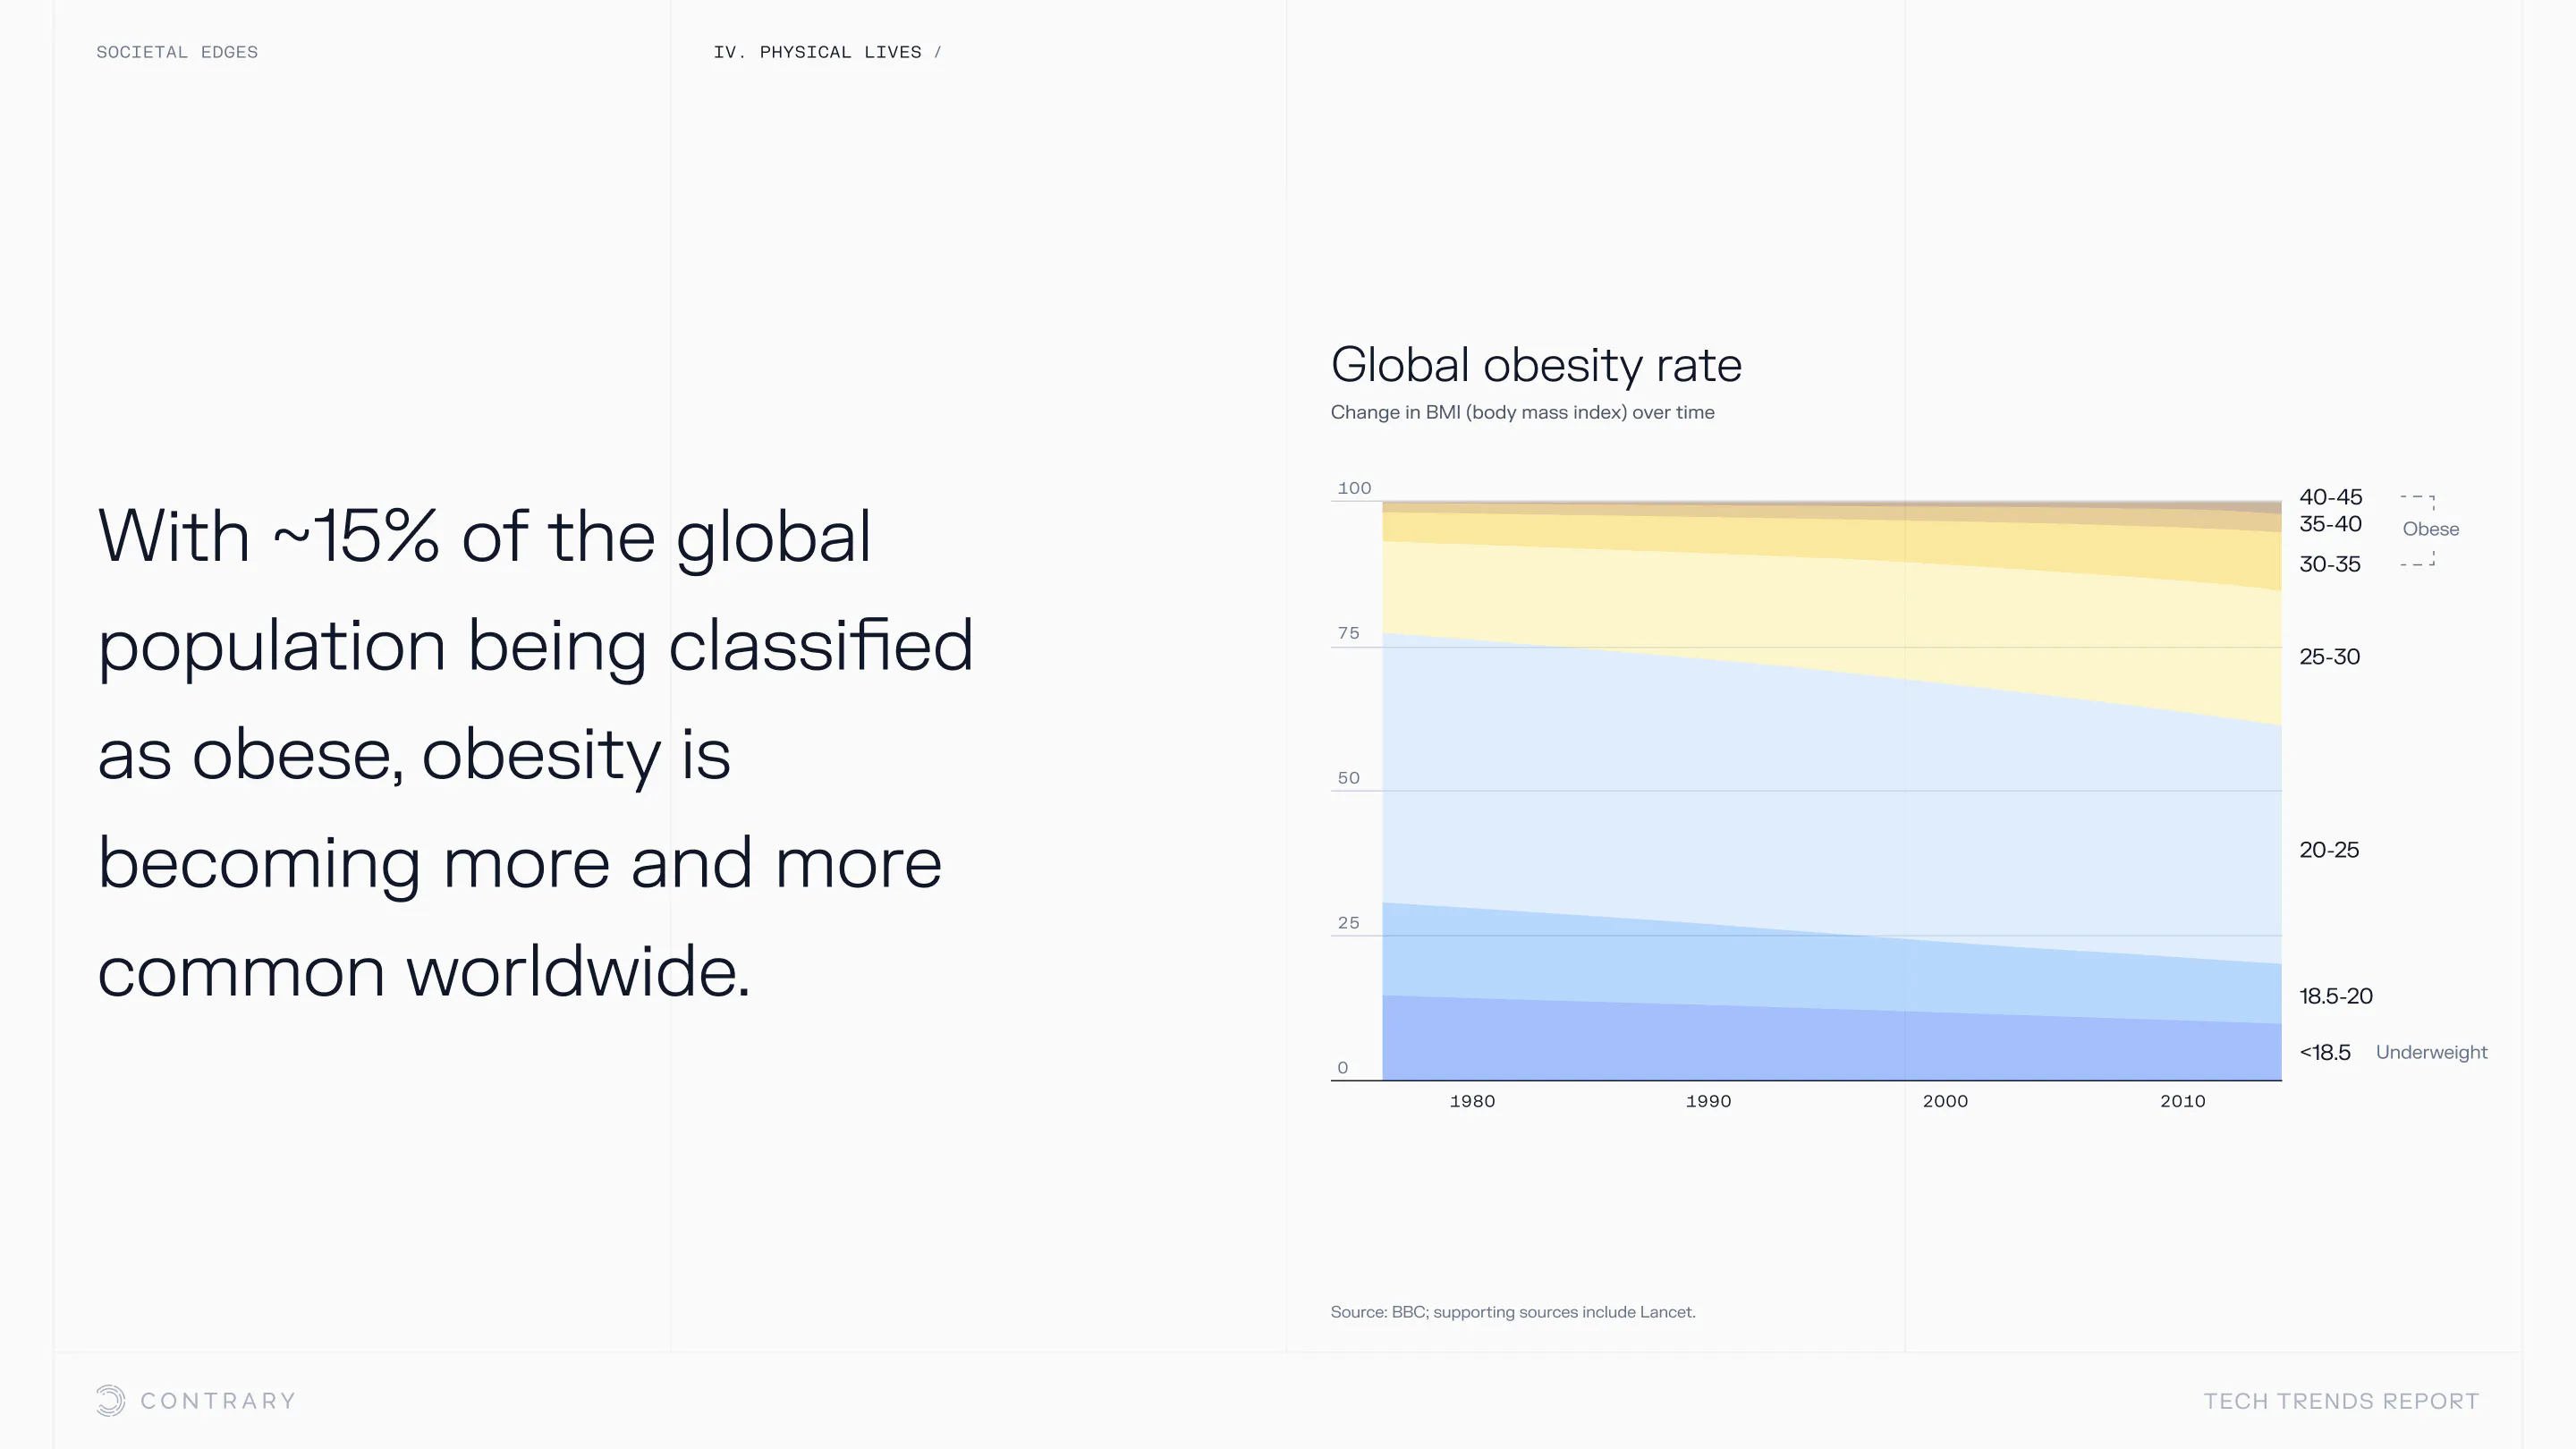

An aging population is bringing up a range of increased concerns, from mental health to disease control. Obesity and gastrointestinal cancers are plaguing younger generations. The cutting edge is tackling a system that has unhealthiness woven into it.